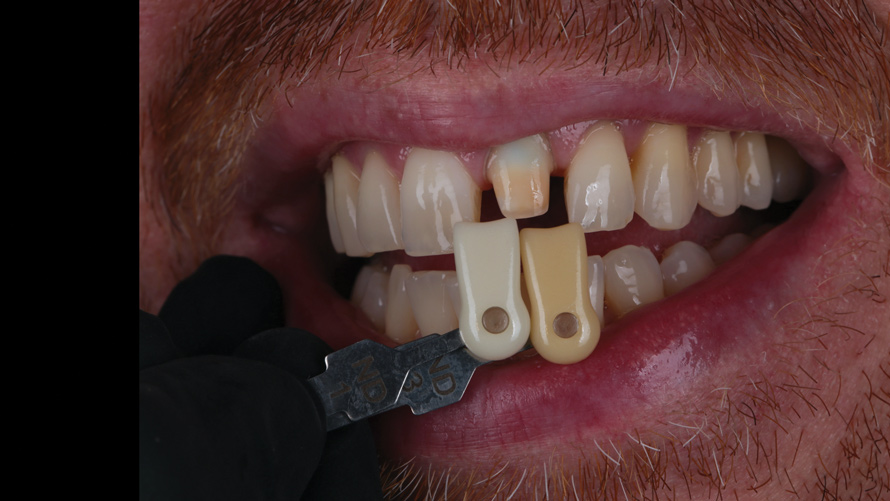

(9.) Case 1: Pre-bleaching and 1-week post-bleaching stump shade evaluations, respectively.

Figure 9

(10.) Case 1: Pre-bleaching and 1-week post-bleaching stump shade evaluations, respectively.

Figure 10

After 1 week, each patient returned for a progress evaluation of the internal bleaching treatment. Intraoral photographs of the stump shade were taken and sent to the ceramist for consultation (Figure 9 through Figure 12). In each case, it was determined that the value of the underlying tooth structure was now adequate and that no additional internal bleaching would be required. All of the zinc oxide/calcium sulfate and bleaching material were then removed, and the root canal sealer and gutta-percha were placed to seal off the canal.

The rapid color transformation achieved significantly decreased the challenge for the dental technician to block out the darkened tooth structure with a ceramic that possessed optical properties similar to natural teeth. In order to allow the dentin color to stabilize, the final stump shade analysis for each patient was made 2 weeks after the internal bleaching procedure. At that time, the pulp chamber was etched with a 37.5% orthophosphoric acid solution, rinsed, coated with an unfilled resin bonding agent, and light cured. The pulp chamber was then filled with A2/A1-colored resin in 2-mm increments and light cured to add "warmth" to the high-value stump shade. A final vinyl polysiloxane impression was made and sent to the laboratory for fabrication of an indirect all-ceramic restoration.